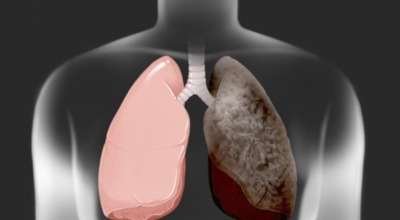

폐암의 공통적인 위험 요소로 손꼽히는 이유 중 하나가 바로 흡연입니다. 흡연자는 비흡연자에 비해 폐암 발병 확률이 수십 배나 높다고 하며, 흡연을 해온 기간이 길수록 그 위험은 더욱 커집니다. 하지만 흡연자라 하더라도 금연을 하면 폐암 발병 확률이 빠르게 낮아진다고 하니, 폐암이 걱정되신다면 무엇보다 먼저 금연이 필수입니다.

간접흡연 외에도 공사장과 같은 환경에서 미세먼지나 석면, 비소, 라돈, 카드뮴 등 인체에 해로운 물질에 노출될 경우에도 폐암이 발생할 수 있다고 합니다. 또한 유전적인 요인으로도 폐암이 발병할 수 있는데요, 가족 중 폐암을 앓았던 분이 있다면 그렇지 않은 경우에 비해 약 2배 정도 폐암에 걸릴 확률이 높다고 해요. 이처럼 폐암은 본인도 모르는 사이에 발병할 수 있기 때문에, 평소 자신의 신체 상태를 자주 확인하고 이상 징후가 있을 때 조기에 발견하는 것이 무엇보다 현명합니다.